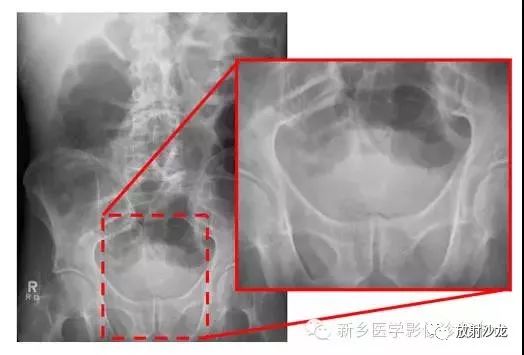

腹部平片解剖